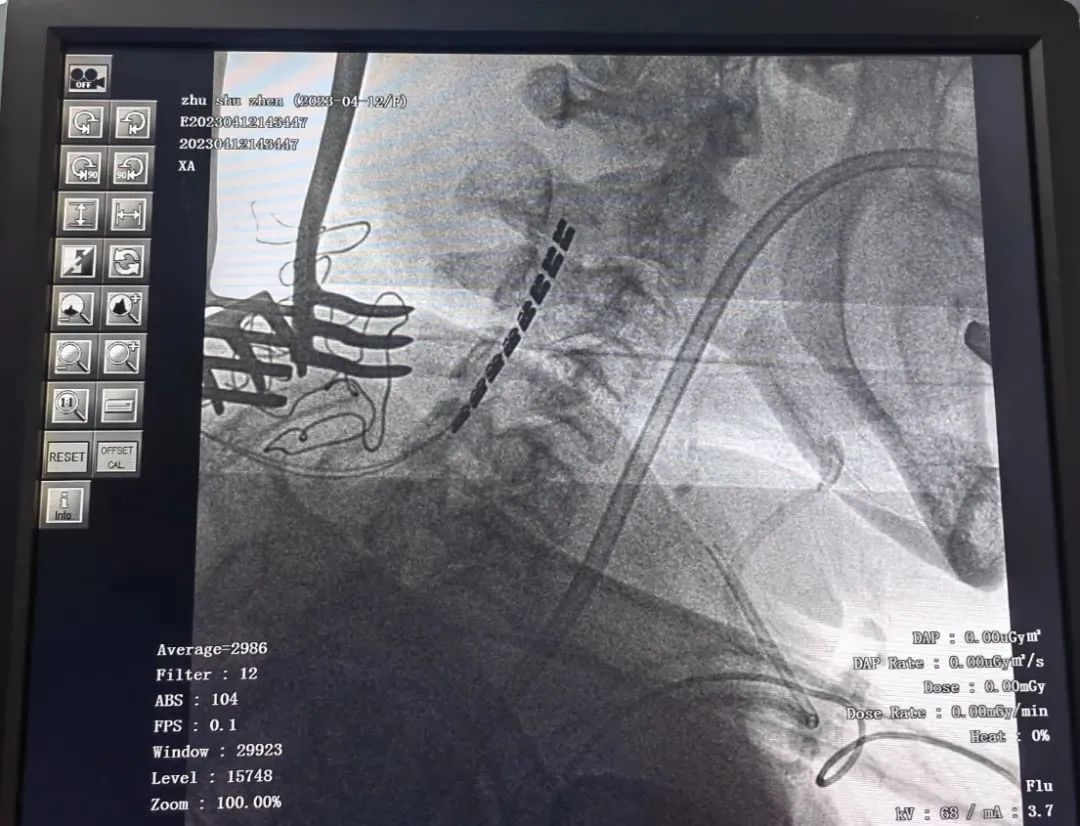

近日,杭州明州姑娘桥康复医院成功开展了3例脊髓电刺激神经调控手术,新技术新业务的持续开展与应用,将为这类慢性意识障碍患者及家属带来新的希望!

(2)患者朱某,中年女性;既往有“系统性红斑狼疮”20年,心跳呼吸骤停复苏术后,意识不清7月余;

患者入院后,由姑娘桥康复医院神经电调控评估小组(康复治疗科主任、HDU一病区主任、影像科主任),通过昏迷恢复量表(修订版)(Coma Recovery Scale-Revision, CRS-R)+神经影像学(MRI、PET CT)+神经电生理评估(EEG、诱发电位),不同阶段反复评估,判定患者处于微意识状态(MCS),决定给予脊髓电刺激术,改善患者意识水平。

高位脊髓电刺激(SCS)是通过电极刺激高位颈髓发送电刺激脉冲,增强脑干上行网状激活系统的神经冲动,改善神经传导状态;同时调节交感神经的活动,增强全脑血流,改善神经代谢及神经递质释放,综合提升患者意识水平。

脊髓电刺激术治疗昏迷患者具有微创、可控、无明显副作用的特点,临床资料显示大约有30%-40%的促醒率。